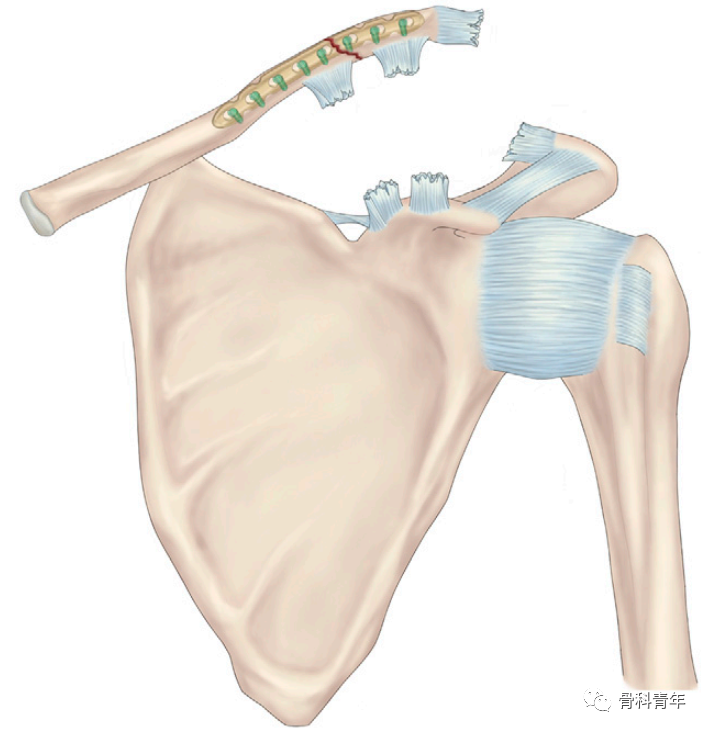

为此,有学者提出采用锁骨钢板+锚钉联合固定的方法,下图所示一例锁骨中段骨折合并同侧IV型肩锁关节脱位患者:

先采用锁骨解剖钢板固定锁骨骨折,复位脱位的肩锁关节后,在喙突置入两枚金属锚钉,并将锚钉自带缝线分别穿过锁骨钢板螺钉孔,在锁骨前方及后方分别打结固定,最后采用缝线直接缝合肩锁韧带及喙锁韧带: